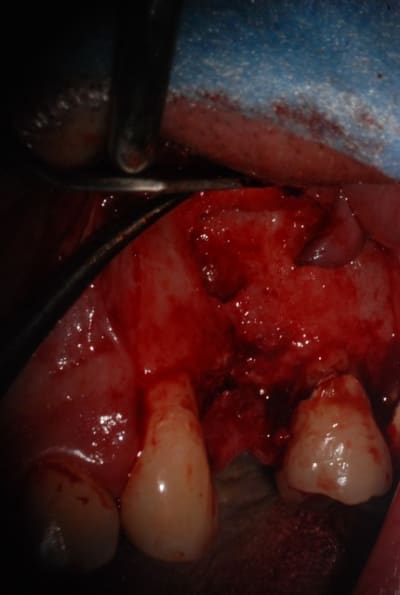

J'ai pas encore le scan

La corticale vestibulaire est présente sauf en regard de la lésion

L'occlusion est en classe I

Est ce que c'est raisonnable de faire une implantaion immédiate le jour de l'extraction avec un bon curetage de la lésion ?

T'as beaucoup de hauteur d'os au dessus de ta lesion, alors...pourquoi pas si t'es bon en largeur, et que tu garde des tissus mous en bon etats.

Tu peux envisager l'extraction implantation en curetant bien mais fais bien attention tu as apparamment aussi une lésion sur la dent adjacente.

Tu pourrais avoir un échec à cause de cette lésion que tu n'aura pas traitée et non pas à cause de ton extraction implantation.